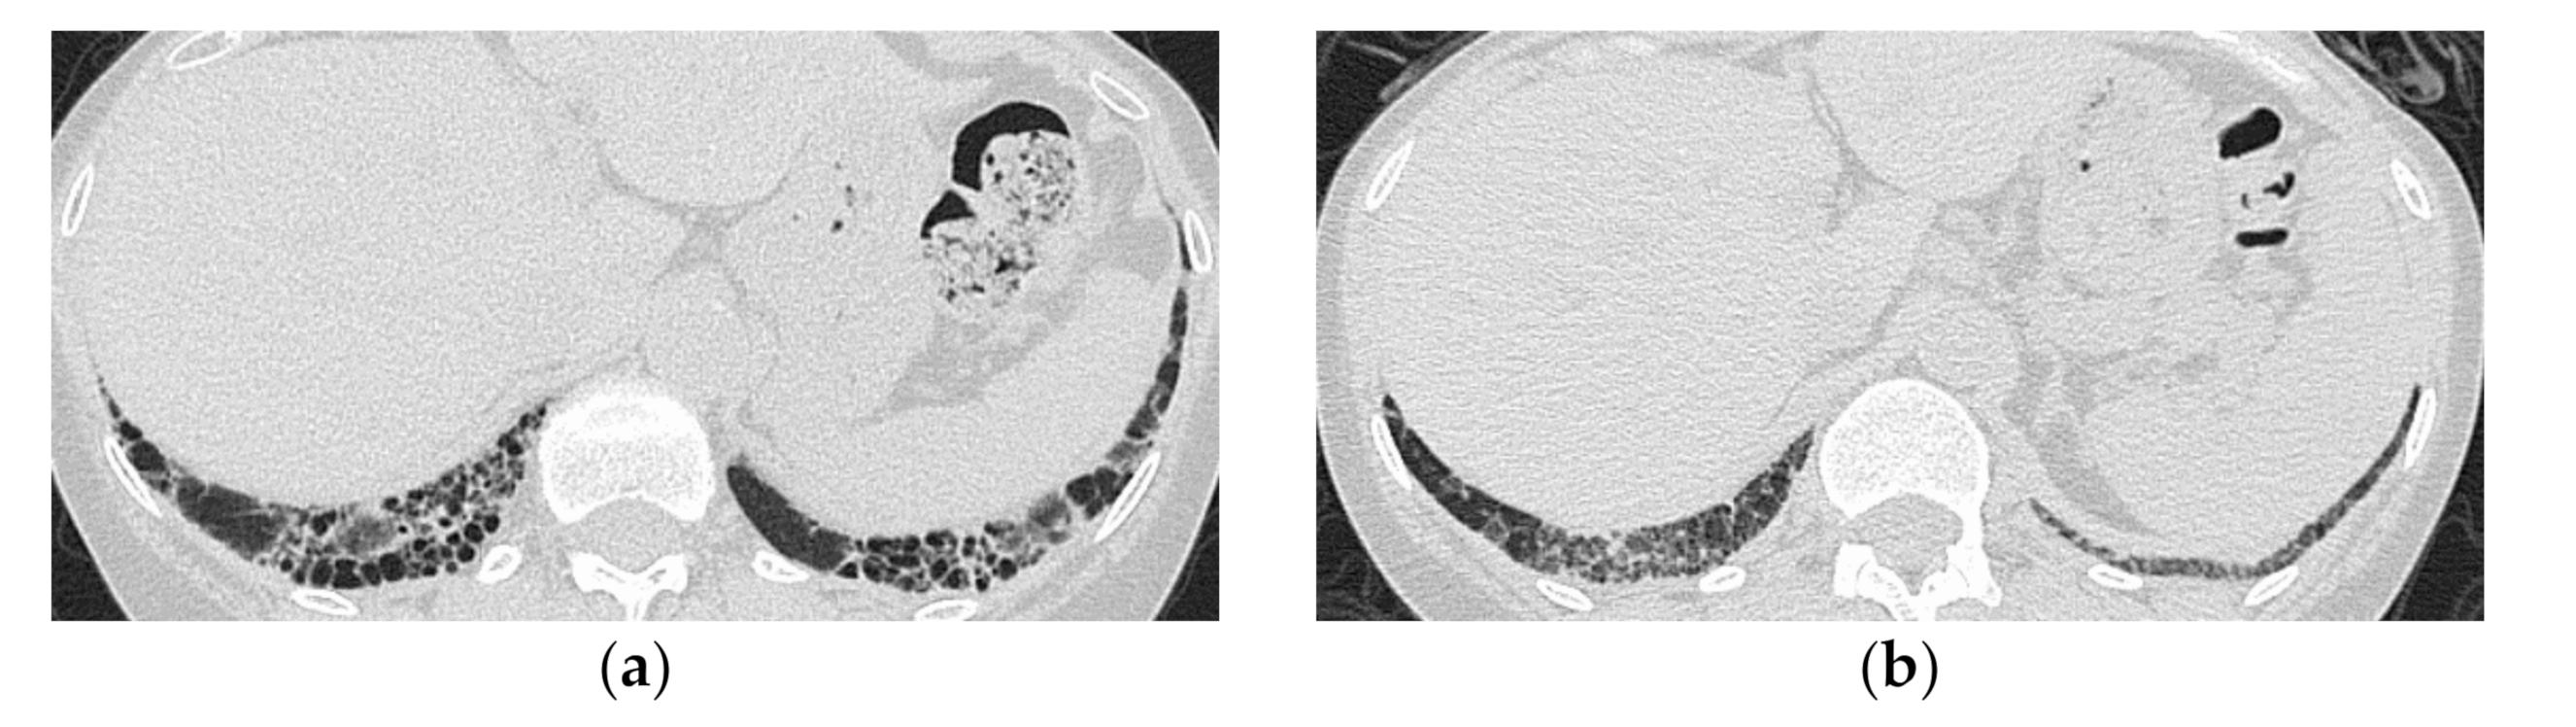

HRCT Findings of Patients with Anti-ARS Ab

| Reduced volume of the lower lobes | Peribronchovascular lesion of the periphery of lower lobes, with parallel spread to the pleura |

| Reticular shadows or consolidation > GGO | Patchy distribution |

| Good response to treatment but relapses | GGO and consolidation |